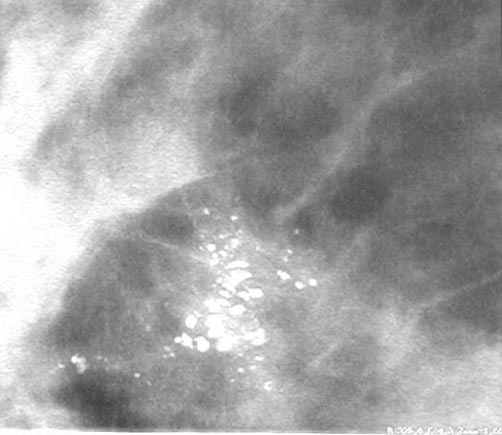

عند النساء الشابات، قد يكون الثدي كثيفًا.

مع تقدم المرأة في العمر، يحدث ارتشاح دهني للثدي يرتبط بضمور الأنسجة الغدية.

تكون الدهون شفافة ومظلمة في تصوير الثدي بالأشعة السينية.

الأنسجة الغدية والسرطانية كثيفة وبيضاء في تصوير الثدي…